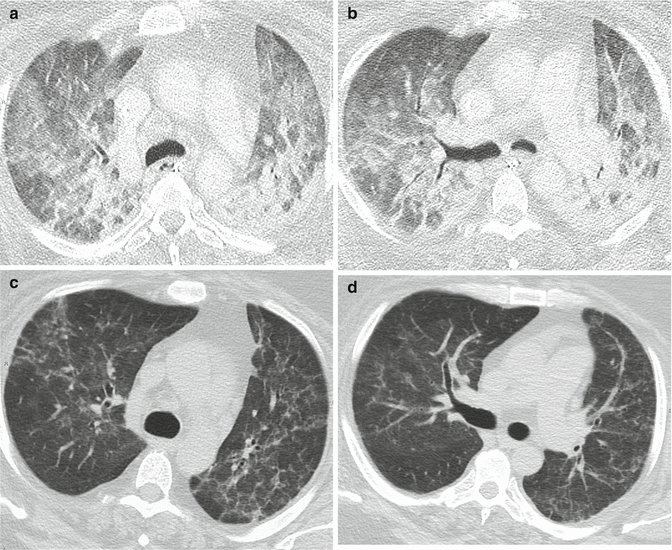

Chest CT images showing lung parenchymal involvement in individuals Is Lung Parenchyma Dangerous It can cause complications like. Pulmonary fibrosis is a lung disease that occurs when lung tissue becomes damaged and scarred. The author’s impression is that. Lung parenchymal diseases can cause permanent damage to the lungs that cannot be cured. In 10% to 12% of all serious injuries, collateral damage involves pulmonary parenchyma. Interstitial lung disease is also called diffuse parenchymal. Is Lung Parenchyma Dangerous.